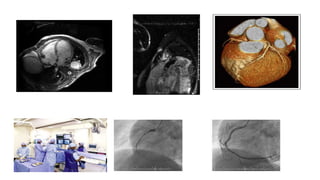

L ’échocardiographie

• Diagnostic de l’IC

• Mécanisme de l’IC

• Etiologie

• Pressions de remplissage

• Surveillance & évolution

• Ajustement du traitement

Echocardiographie

AUTRES